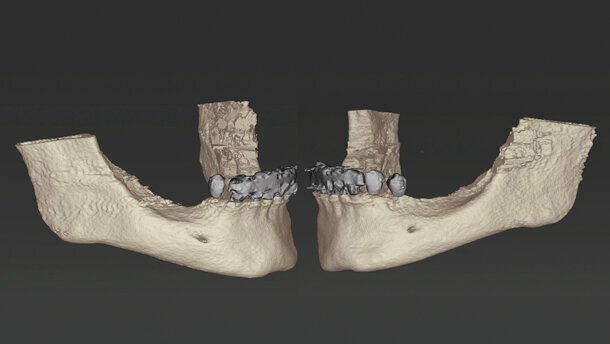

Paziente donna, di 71 anni, non fumatrice, in un buono stato di salute generale e nutrizionale si presenta con molteplici restauri protesici nella zona mascellare, composti da ponti e corone singole posizionate in tempi diversi. La mandibola rivela una tenuta protesica insufficiente. Il dente 43 è stato distrutto, sotto la corona, da una carie e ha subito un trattamento del canale radicolare (Fig. 1). La paziente ha richiesto ora la riabilitazione con una protesi fissa. La conseguenza di anni di utilizzo di protesi rimovibili, ha fatto sì che la mandibola risentisse di un problema di atrofia/riassorbimento di classe V-VI sulla destra e di classe IV-Cawood sulla sinistra1.

È stata discussa con la paziente la possibilità di un aumento osseo con materiale autologo prelevato dalla regione retromolare dei rispettivi lati e un successivo impianto. La paziente ha quindi richiesto una radiografia 3D preoperatoria (Fig. 2) per chiarire la necessità di questa procedura. È stata consigliata, dopo l’aumento, una pianificazione tridimensionale del trattamento implantare con coDiagnostiX (Dental Wings) per il posizionamento dell’impianto e un ripristino immediato tramite Multi-Base Abutments (Straumann).